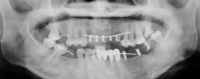

用手術定位板來照X光